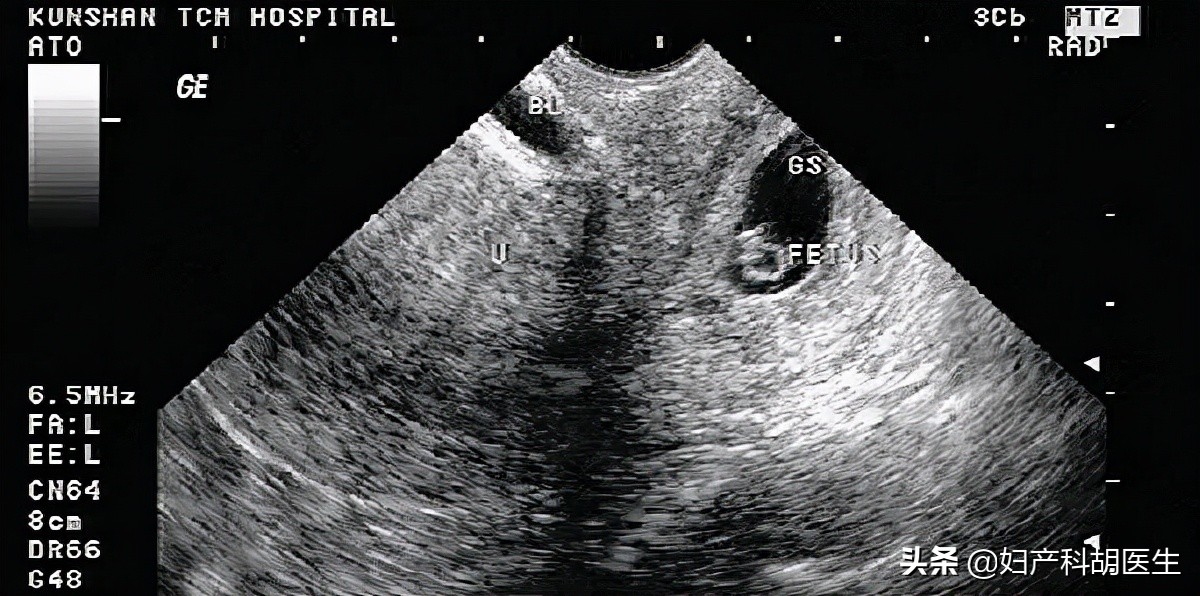

停经 55 天时自测尿 HCG(+),无腹胀及阴道出血。在妇科门诊就诊,诊断早孕,要求流产。术前检查血常规,凝血功能均无异常,B 超提示:孕囊大小 34×15 mm,胚芽长 10 mm,见心管搏动,孕囊位置偏下,靠近子宫峡部。查体无特殊。

B 超如下所示: